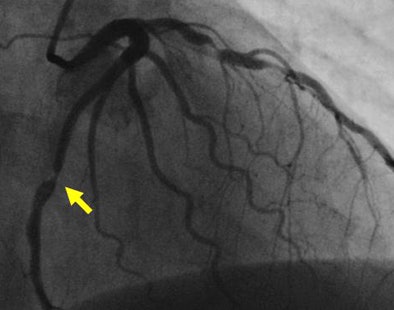

| Stenosis in left anterior descending artery detected at CT angiography (above) is confirmed at angiography (below). Images courtesy of Dr. Matthew Budoff. |